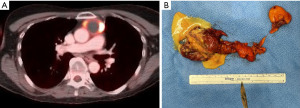

Also, an incisional biopsy in a patient with a solitary, well circumscribed, solid, non-invasive (encapsulated) and resectable mediastinal tumor on preoperative imaging and with negative tumor markers is contraindicated in order to avoid tumor spilling that may increase the risk for pleural tumor spread during late follow-up. This is especially the case for TET. Primary resection without preoperative tissue diagnosis is then advocated (Figure 1A). In a survey of members of the European Society of Thoracic Surgeons reported in 2011, the uselessness of a routine histologic confirmation before surgery was queried. Ninety one percent of the responding centers do not routinely look for histological confirmation when thymoma is suspected. The most frequent comment was that in case CT scan strongly suggests the presence of a thymoma (small, resectable, encapsulated lesion with no radiological sign of invasion) or when MG is associated, no preoperative histological diagnosis is required (18). Similarly, a well circumscribed lesion in the posterior mediastinum suspicious of a benign neurogenic tumor can be resected primarily without previous biopsy when resection is indicated.

On the other hand, a surgical biopsy for histopathological, immunohistochemical and molecular analysis is indicated in patients presenting with an irregular, lobular, large tumor invading mediastinal structures (Figure 1B). Also in patients with a mediastinal mass and elevated AFP or β-HCG serum levels indicative for the presence of an extragonadal germ cell tumor, a biopsy of the mass for further analysis may occasionally be needed to exclude morphologic mimics presenting in the mediastinum. It has been reported that solitary fibrous tumor, Ewing sarcoma, or rhabdomyosarcoma may also produce elevated AFP or β-HCG serum levels (19). However, a surgical biopsy may delay needed preoperative chemotherapy and make subsequent surgery more difficult.